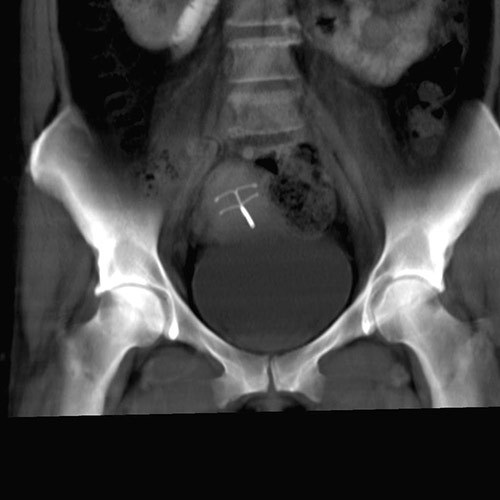

En kvinne i slutten av 40-årene ble innlagt på kirurgisk avdeling grunnet magesmerter. Standard CT-undersøkelse av abdomen/bekken viste ingen årsak til pasientens smerter, men som bifunn ble det påvist to spiraler i uterinkaviteten, her presentert som 3D-rekonstruksjon (bildet til venstre) og tykk multiplanrekonstruksjon (bildet til høyre) av CT-opptaket. Ved søk på PubMed finner vi bare ett liknende rapportert tilfelle av to spiraler i uterus (1).

Pasienten ble henvist til gynekologisk poliklinikk for uthenting av spiralene. Ved transvaginal ultralyd verifiserte man to spiraler. Den ene, en hormonspiral, var enkel å fjerne, da trådene var synlige ved cervix. Trådene til den andre spiralen, som var en kobberspiral, ble funnet et stykke opp i cervixkanalen. Spiralen ble fjernet ukomplisert.